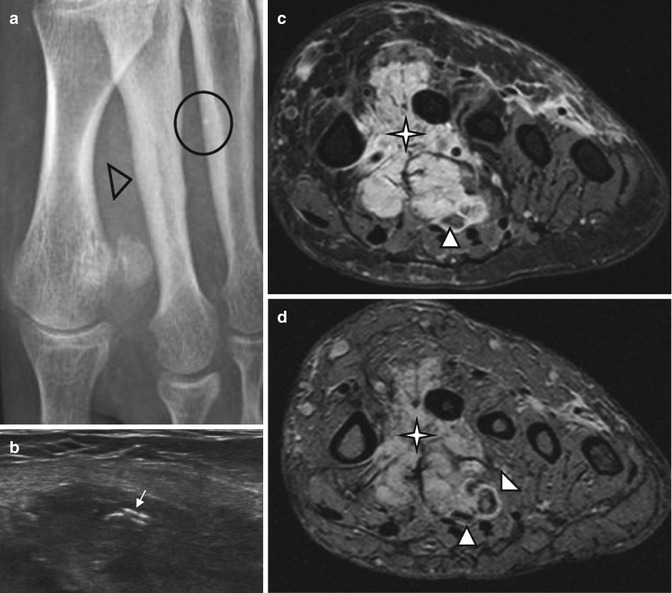

Venous malformation of the left plantar region. (a) Plain radiograph. (b) Axial ultrasound. (c) Axial spin-echo T2-weighted MR image, with fat suppression. (d) Axial gradient-echo T2-weighted MR image. (a) Plain radiography demonstrates periosteal reaction, probably related to chronic vascular stasis (black arrowhead), and phlebolith (circle). This finding is characteristic of intramuscular venous malformation. (b) US shows hypoechogenic soft-tissue lesion with hyper echogenic foci with posterior acoustic shadowing corresponding to phleboliths (arrow). (c, d) Spin-echo and gradient-echo T2-weighted images show the VM as multiple slightly hyperintense serpiginous channels (star) with rounded hypointense phleboliths (white arrowheads), extending within the plantar muscles